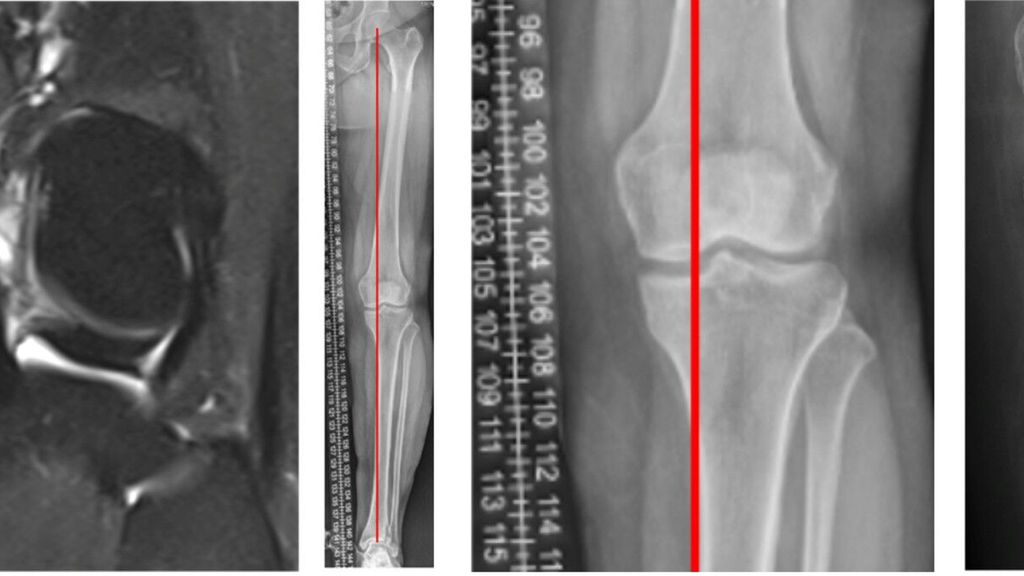

Angeborene Fehlstellungen des Unterschenkels

Kongenitale Deformitäten des Unterschenkels gehören zu den seltenen, aber medizinisch bedeutenden und operativ herausfordernden Diagnosen der Kinderorthopädie. Eine differenzierte ...

Korrektur assoziierter Gelenkspathologien beim kongenitalen Femurdefekt

Der kongenitale Femurdefekt ist eine der spannendsten und komplexesten angeborenen Fehlbildungen in der Kinderorthopädie und in der klinischen Präsentation sehr vielgestaltig. Während ...